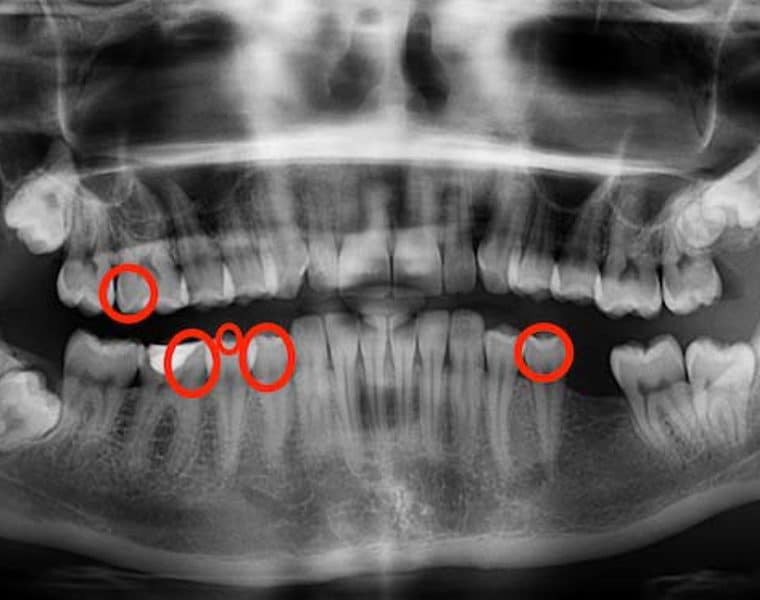

How I Reversed 5 Cavities in 3 Months

You can reverse dental decay and your teeth can remineralize, and I am living proof of that. For most of my life, I had perfect dental health. As a child, I never…